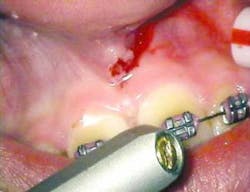

The following is a case report of one such procedure using the Opus Duo, a dual Er:YAG and CO2 dental laser system. This case begins with the diagnosis of a frenal attachment connected to the interdental papilla between maxillary central incisors (No. 8 and No. 9). The muscle attachment is bulky, and would inhibit further orthodontic correction. This patient was referred by her orthodontist for a minimally invasive laser frenectomy procedure before the next stage in her orthodontic treatment (figure 1).

After infiltration of 1cc of local anesthetic solution, the Er:YAG laser (OpusDuo, OpusDent USA) was used at 350mj with a 1,000-micron, contact sapphire tip and heavy water spray to gently ablate the frenal attachment and underlying muscle tissue down to the level of the periosteum (figures 2, 3, and 4). Once this is accomplished, there is a small defect in the vestibular mucosa and interdental papilla where the frenal attachment and muscle once was. There is no charring, no burned tissue, and free bleeding in the site (figure 5).